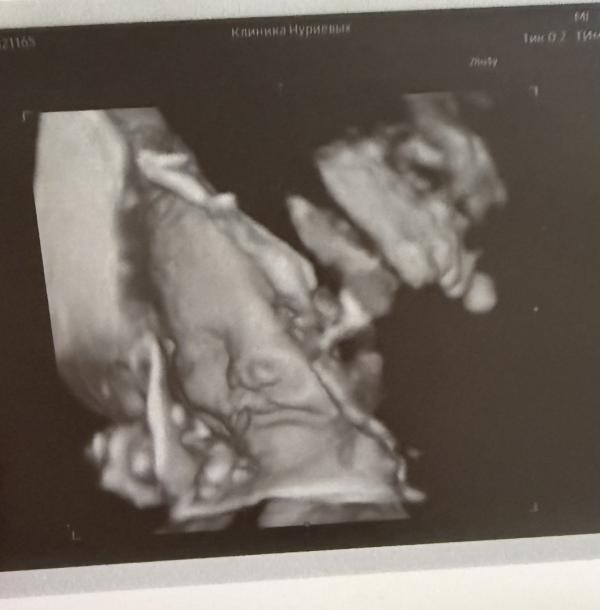

За то распечатали мне фото нашей малышки🩷

29 недель 🙏